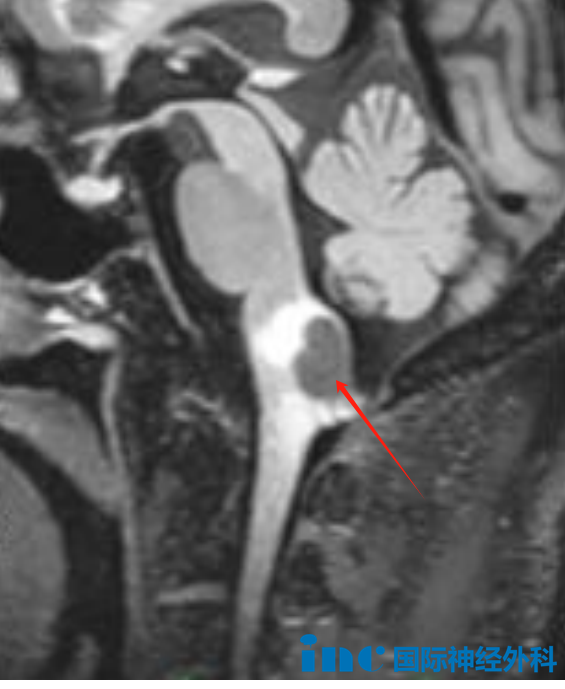

当陈先生发现小指麻木时,他以为只是颈椎问题。谁曾想,这场“麻木风暴”在两个月内向全身蔓延。进一步检查的结果如同惊雷:延髓背侧占位性病变正在蚕食他的“生命中枢”。病变位于延髓这一关键生命区域,并造成占位效应,脑干内存在弥漫性水肿,因此明确需要进行手术治疗。

然而,在延髓区域,绝大多数患者面临着这样的困境:“没有医生愿意为我手术!延髓肿瘤切除手术是在‘赌命’,就算成功切除大概率要长期卧床靠呼吸机生存,甚至,很可能会在手术台上永远醒不过来……”面对这一度被称为“手术禁区”的区域,巴教授却给出了截然不同的答案:“唯一可取的治疗方案是手术切除,而且这类手术对我而言难度不大。”

30年深耕脑干手术的经验,让这位国际神外大咖能够游刃有余地在“生命禁区”精准操作。在他手中,延髓肿瘤手术不再是“赌命”,而是一场精心策划的“生命保卫战”。从术前手术入路设计,到显微镜下毫厘不差的精细操作;从神经功能的保全,到术后重归正常生活——他不断突破着一个又一个曾被视为禁区的医学极限。